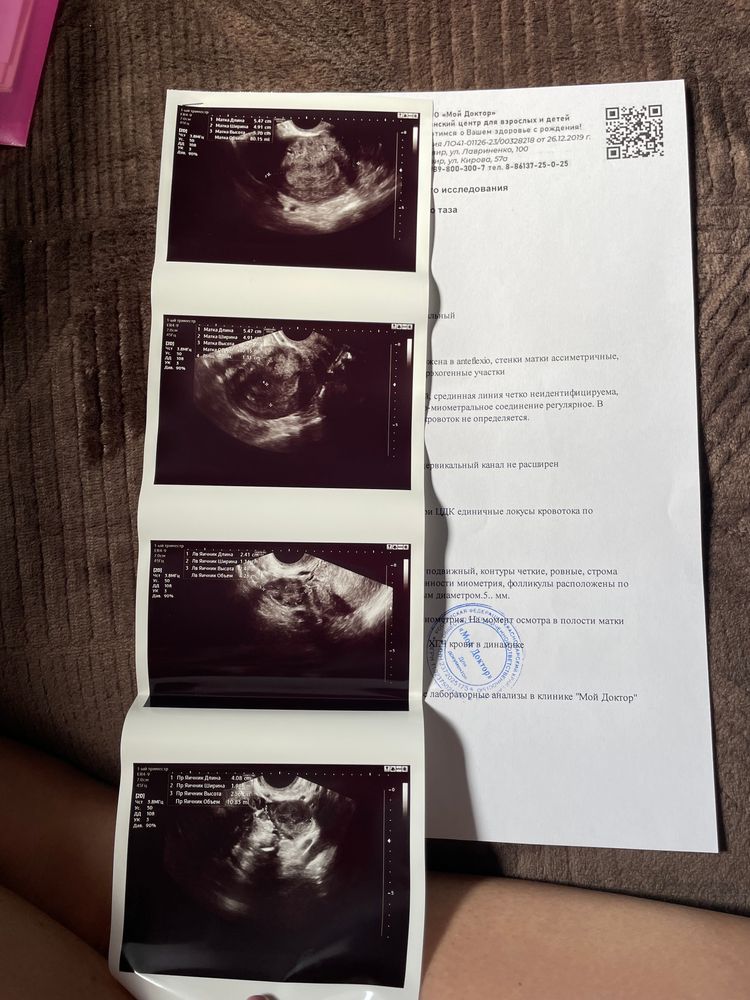

УЗИВчера была на узи, позавчера хгч 959, пошла по поводу выделений, ярко розовых, пила дюф и транексам, все просто, дюфастон оставили транексам отменили

Не нашли Пя, очень страшно что при таком хгч не нашли

ни где не колит, ни болит, но все в целом настораживает, и кровь, и то что пя не нашли

Кто то понимает по узи? Стоит расчитывать на благоприятный исход?

Марина, спасибо🫶🏻 уже нашли, сходила туда же к Бареевой

Поставили 5 недель, сказали прийти через 10 дней